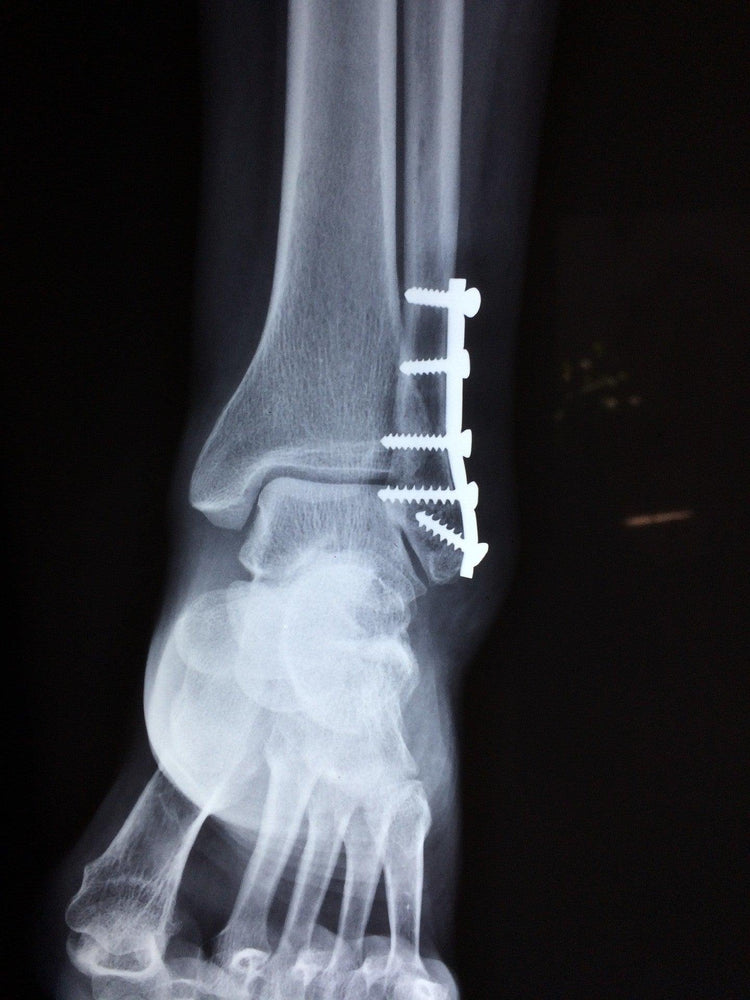

Physicians conduct image and stress tests in order to determine the kind of treatment required. X Rays, CT scan or MRI scan may be conducted to analyze the position of the ankle while physical stress tests depict the stability of the ankle. This determines whether you require ankle surgery or any non surgical treatment.

Surgical treatment involves detailed standard medical procedures which reposition the bones and then holds them with the use of screws or if necessary metal plates and rods depending on the bones involved.